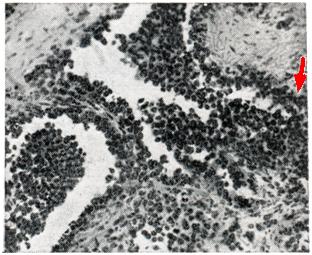

Ангиоэндотелиома (микропрепарат). Пролиферация эндотелия сосудов (указана стрелкой).

Микроскопически ангиоэндотелиома имеет разнообразное строение, но чаще напоминает структуру пролиферирующей капиллярной ангиомы. Между атипичными кровеносными сосудами и в их просветах, в той или иной степени заполненных кровью или белковыми массами, располагаются очаги пролиферирующего эндотелия, формирующего солидные тяжи и альвеолярные комплексы (рис.). Иногда опухолевые клетки целиком заполняют просвет атипичных сосудов, и ангиогенную природу опухоли удается установить только с помощью метода импрегнации, выявляющего сосудистые мембраны. Гистогенез связывают с сосудистым эндотелием, адвентициальными камбиальными элементами и зародышевой ретикулярной тканью. Клиника ангиоэндотелиомы определяется локализацией опухоли и скоростью ее роста. Ангиоэндотелиома мягких тканей конечностей обычно отличаются агрессивным течением и быстро рецидивируют. Метастазирование изучено недостаточно, происходит гематогенным и лимфогенным путями. Лечение чаще комбинированное — облучение с последующей хирургической операцией. В некоторых случаях временный эффект дает химиотерапия алкилирующими препаратами. Прогноз в большинстве случаев неблагоприятный.